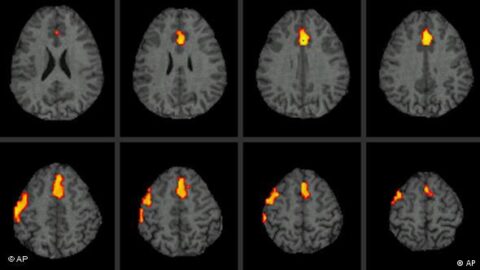

3. 실로시빈의 뇌 내 작용 기전

실로시빈은 세로토닌(5-HT) 유사체로서 뇌의 5-HT2A 수용체에 작용한다. 특히 전두엽 피질과 후방대상피질(posterior cingulate cortex), 기본모드네트워크(default mode network, DMN) 등 자아감 형성에 핵심적인 신경망에 영향을 주어, 기존의 사고 패턴을 유연하게 만드는 것으로 알려져 있다. 우울증 환자의 경우 지나치게 경직된 사고 회로와 반복적 부정 사고 루프가 DMN에서 활성화되어 있는데, 실로시빈은 이 네트워크를 일시적으로 해체해 자아 해체 경험을 유도하고 인지적 ‘재설정(reset)’을 유도한다는 이론이 제기되고 있다.